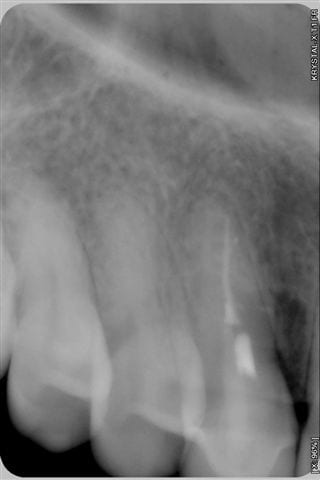

-La seule "nouvelle" technologie qui semble enfin acceptée par le plus grand nombre d'entre nous est l'implantologie, à tel point que des abus sont faits, à savoir extractions intempestives de certaines dents tout à fait conservables grâce à la paro ou l'endo cf radios ci-joint, la dernière ayant été faite un an après le traitement ("madame, votre canine est infectée de façon très importante, on ne peut pas la sauvée, nous allons l'extraire et poser un implant"...)

016 iz9c3d - Eugenol

021 qxjakd - Eugenol

004 s729bo - Eugenol